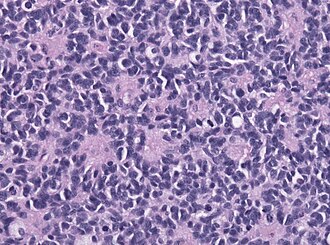

| Caption    = Classic medulloblastoma [[H&E stain]].

Classic medulloblastoma H&E stain.

Features:<ref>URL: [http://moon.ouhsc.edu/kfung/jty1/neurotest/Q93-Ans.htm http://moon.ouhsc.edu/kfung/jty1/neurotest/Q93-Ans.htm]. Accessed on: 26 October 2010.</ref>

*[[Small round cell tumour]].

*Mild to moderate nuclear pleomorphism.

*High mitotic count.

*Homer-Wright [[rosette]]s:

**Rosette with a meshwork of fibers (neuropil) at the centre.<ref>{{cite journal |author=Wippold FJ, Perry A |title=Neuropathology for the neuroradiologist: rosettes and pseudorosettes |journal=AJNR Am J Neuroradiol |volume=27 |issue=3 |pages=488–92 |year=2006 |month=March |pmid=16551982 |doi= |url=}}</ref>